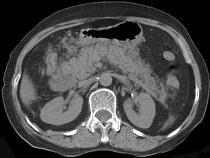

问题 男,30岁,上腹部剧痛,恶心呕吐,压痛反跳痛,血细胞计数升高,血和尿淀粉酶升高,影像表现如图,最可能的诊断是什么 ( )

选项 A.急性肠梗阻 B.胃溃疡穿孔 C.胰腺癌 D.急性胰腺炎 E.慢性胰腺炎

答案 D